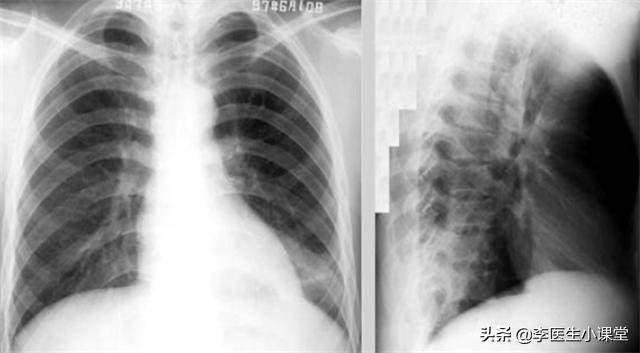

患者体温37.8℃、血压130/85、身高178cm、体重80kg。血常规提示白细胞增加,提示身体存在炎症,肺部CT显示患者右肺下叶及左肺上下叶见斑片状阴影 边界模糊 密度较淡 各级段支气管畅通 纵隔内未见明显肿大淋巴结 双侧胸膜腔内未见明显液体密度影,确诊为肺炎。